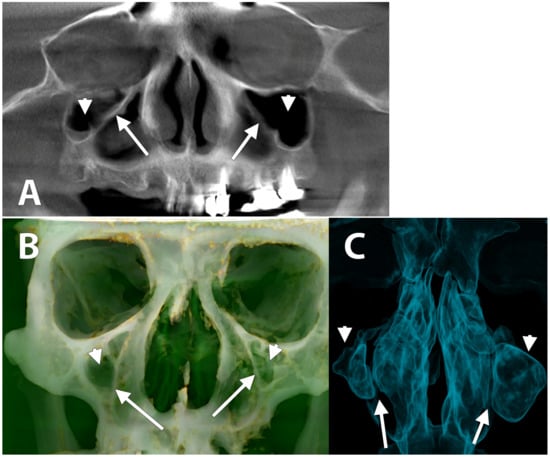

3. Results